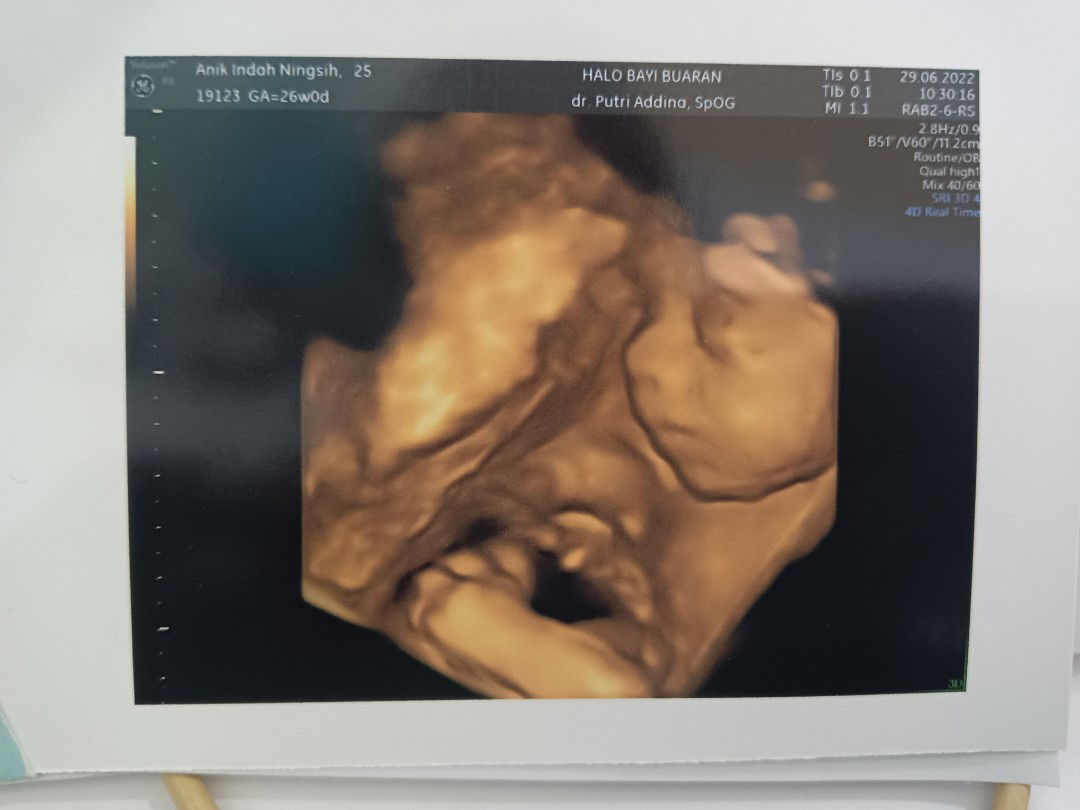

Saya mau tanya moms, saya udah usia kehamilan 20 mg kok perutnya masih kecil yah? Ada yg sama?

Bentuk perut mh ga masalah bun, penting saat priksa dokter perkembangan bagus sesuai khamilan. kbtulan saya juga 20w nihπŸ˜ƒ

iya heheh, soalnya banyak yang ngomong kok ukuran perutnya masih kecil aja huhuhu

kalau usg nya bagus, dan sesuai umur ga usa dipikirin sih ukuran perutnya